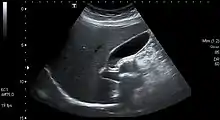

Gallstones form when the bile is saturated, usually with either cholesterol or bilirubin.[18] Most gallstones do not cause symptoms, with stones either remaining in the gallbladder or passed along the biliary system.[19] When symptoms occur, severe "colicky" pain in the upper right part of the abdomen is often felt.[18] If the stone blocks the gallbladder, inflammation known as cholecystitis may result. If the stone lodges in the biliary system, jaundice may occur; if the stone blocks the pancreatic duct, pancreatitis may occur.[19] Gallstones are diagnosed using ultrasound.[18] When a symptomatic gallstone occurs, it is often managed by waiting for it to be passed naturally.[19] Given the likelihood of recurrent gallstones, surgery to remove the gallbladder is often considered.[19] Some medication, such as ursodeoxycholic acid, may be used; lithotripsy, a non-invasive mechanical procedure used to break down the stones, may also be used.[19]

An ultrasound is often the first medical imaging test performed when gallbladder disease such as gallstones are suspected.[19] An abdominal X-ray or CT scan is another form of imaging that may be used to examine the gallbladder and surrounding organs.[19] Other imaging options include MRCP (magnetic resonance cholangiopancreatography), ERCP and percutaneous or intraoperative cholangiography.[19] A cholescintigraphy scan is a nuclear imaging procedure used to assess the condition of the gallbladder.[26]